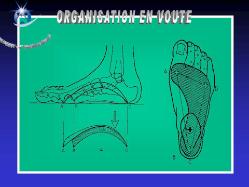

Anatomie du pied

Le squelette du pied est composé de 28 os qui se combinent en de nombreuses articulations.